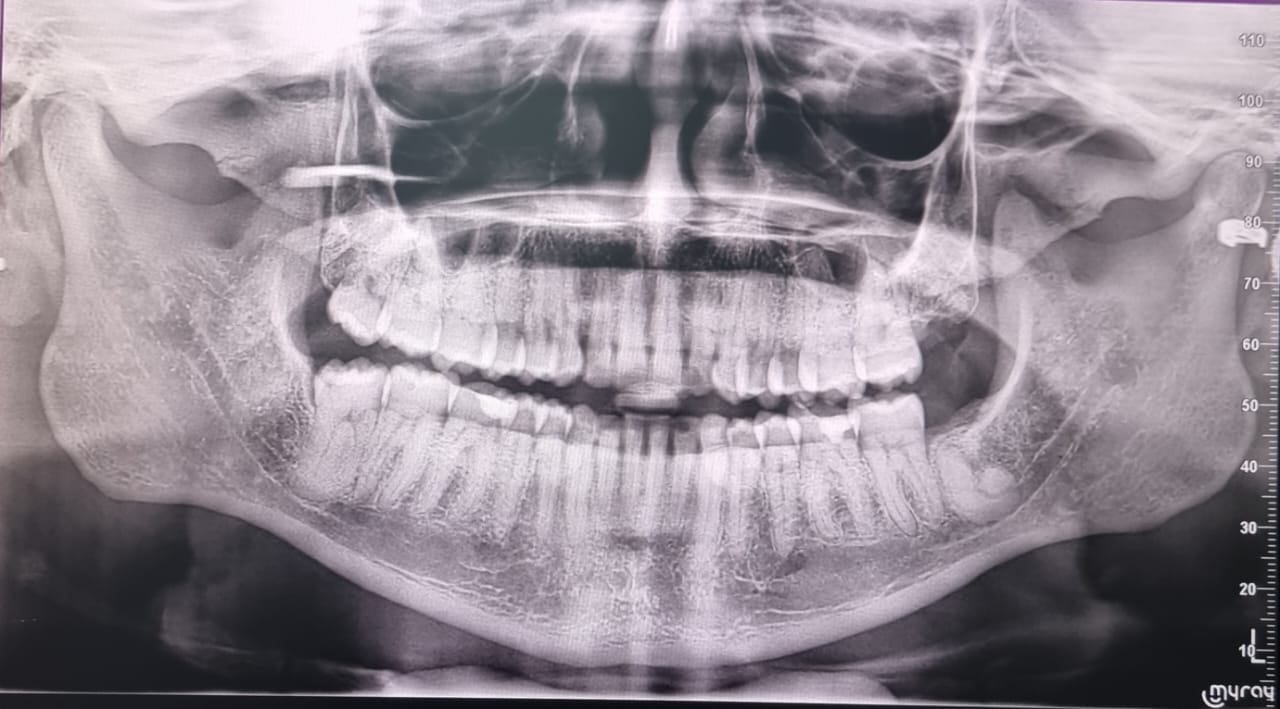

How To Read Dental Panoramic XRay at Carmen Rivera blog Teeth X Ray Left Or Right    here are some quick tips from mary berg, rvt, vts (dentistry) on figuring out which way is up in dental imaging. The more thick and dense the material is, the. Here is a picture of what a. The right teeth are on your left, the. This is useful, as your dentist can recommend certain treatments (for example, braces, implants,. Teeth X Ray Left Or Right.

Panoramic xray image of teeth and mouth with wisdom teeth Parkview Teeth X Ray Left Or Right    here are some quick tips from mary berg, rvt, vts (dentistry) on figuring out which way is up in dental imaging. The right teeth are on your left, the. This is useful, as your dentist can recommend certain treatments (for example, braces, implants, or wisdom teeth removal) based on your results.  position the images as if you are. Teeth X Ray Left Or Right.

Panoramic dental tooth Xray. Radiography for dental structures Teeth X Ray Left Or Right  The right teeth are on your left, the.  position the images as if you are standing in front of your patient, looking them in the face. This is useful, as your dentist can recommend certain treatments (for example, braces, implants, or wisdom teeth removal) based on your results. Here is a picture of what a. The more thick and. Teeth X Ray Left Or Right.